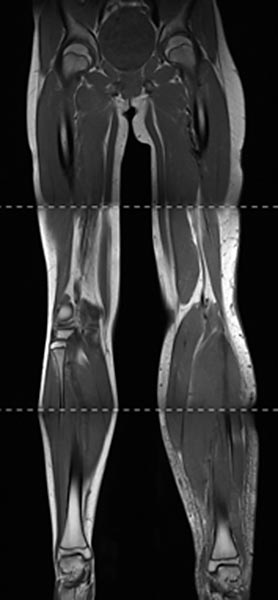

Zusammengesetzte, T1-gewichtete koronare MRT vom Becken bis zu den Füßen. Gut sichtbar hier nicht nur die Beinlängendifferenz (ossäre Hyperplasie), sondern auch die links deutlich größere Muskulatur und das vergrößerte Fettgewebe. Die Hyperplasie der Extremität betrifft beim Parkes-Weber-Syndrom alle Gewebe.

Koronare, T2-gewichtete, fettunterdrückte MRT der Unterschenkel beidseits. Auf der betroffenen linken Seite ausgeprägtes subkutanes Ödem durch den chronischen Venenhochdruck.